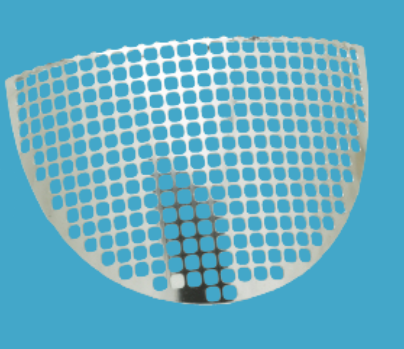

TELA REFORÇO PARA TETO ACETABULAR

Aproveitando a importante experiência adquirida, a Tela para Reforço foi projetada e fabricada para reforçar as áreas afetadas por lesões ou doenças degenerativas. A Tela para Reforço é uma estrutura fabricada em aço inoxidável ASTM F 139 utilizada para contenção de estruturas ósseas do tipo femoral e/ou acetabular, reparando defeitos da parede do fêmur, do teto ou fundo do acetábulo. Sua fixação pode ser feita através de Parafusos e/ou Cabo de Aço/Fio de Cerclagem.

A Tela de Reforço Incomepe se apresenta em diversas variações de tamanho, que são configuradas através de sua aplicabilidade.